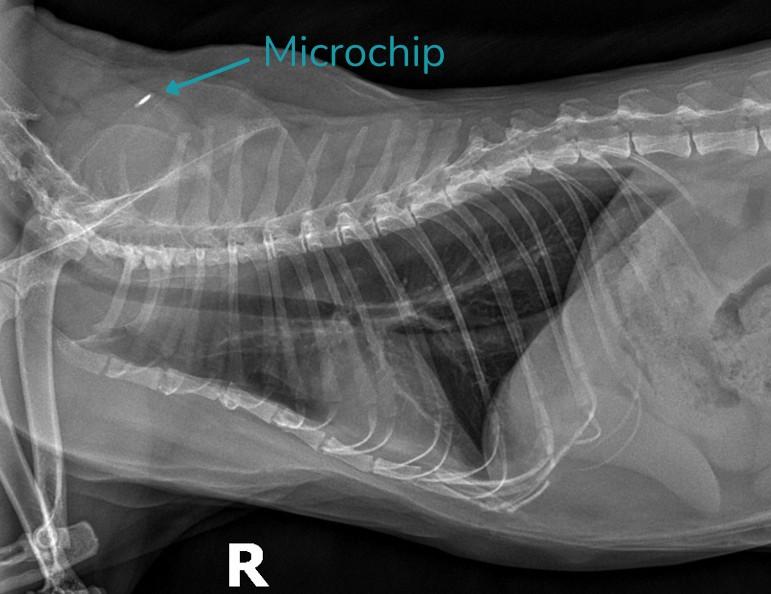

Cat X-Ray Showing a Microchip

A microchip is a small, electronic device about the size of a grain of rice that is implanted just beneath your pet’s skin, typically between the shoulder blades. Each microchip contains a unique identification number that links to your contact information in a secure database. Unlike collars or tags, a microchip cannot fall off or be removed, making it a reliable form of identification for pets of all species.